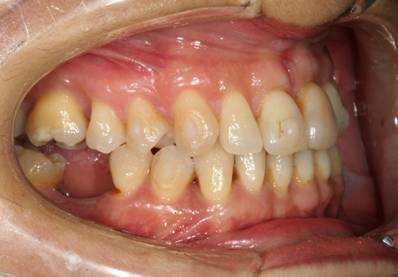

Trattamento soggetto adulto parodontopatico - Trattamento con mascherine invisibili

Il trattamento ha previsto l'utilizzo di 20 mascherine per l'arcata superiore e 13 per l'arcata inferiore.